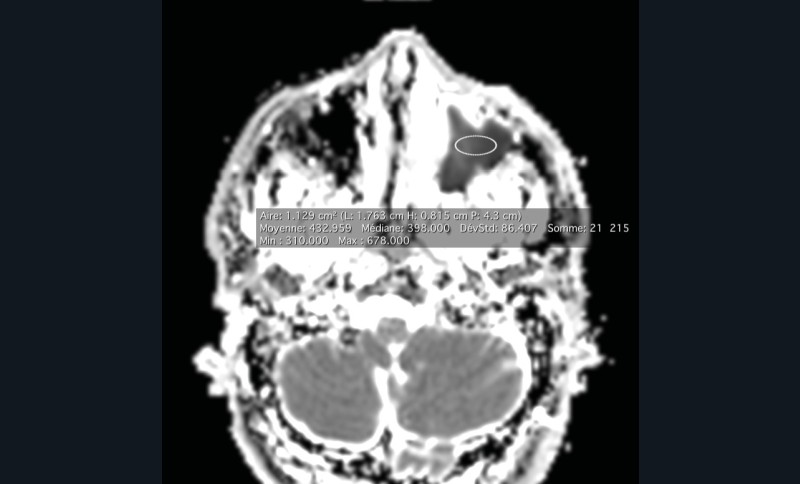

La tomodensitométrie des sinus retrouve un comblement complet unilatéral du sinus maxillaire gauche et des cellules ethmoïdales antérieures homolatérales, sans image de densité calcique intrasinusienne et sans lyse osseuse des parois (fig. 1). L’IRM montre un épaississement tissulaire de 23 mm de grand axe en regard du méat moyen gauche, avec un aspect de signal T2 hétérogène (fig. 2) et prenant le contraste en masse (fig. 3). Le comblement maxillaire gauche associé à un épaississement muqueux en cadre rehaussé correspond à une rétention en hypersignal en diffusion (fig. 4), avec diminution du coefficient apparent de diffusion (moyenne à 433 mm2/s) en faveur d’une pyocèle (fig. 5).